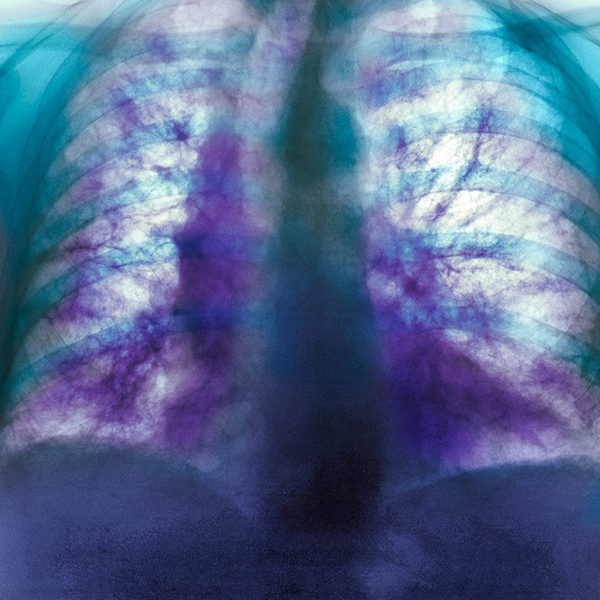

Figure 1: Colored x-ray of the chest of an 82-year-old man with idiopathic pulmonary fibrosis. RIKEN researchers have developed a mouse model that closely mimics the human condition. © SCIENCE PHOTO LIBRARY

Idiopathic pulmonary fibrosis (IPF) is a progressive lung disease in which scarring of the lungs makes breathing increasingly difficult. The cause is unknown with no cure, and it often leads to eventual death.

Now, Moro’s team has shown that these mice mimic the progression of IPF more closely than other mouse models of the lung disease. In particular, unlike traditional mice models—where lung damage originates within the airways—these mice exhibit scarring on the lung’s lining (pleural side), mirroring the pathology observed in IPF patients.